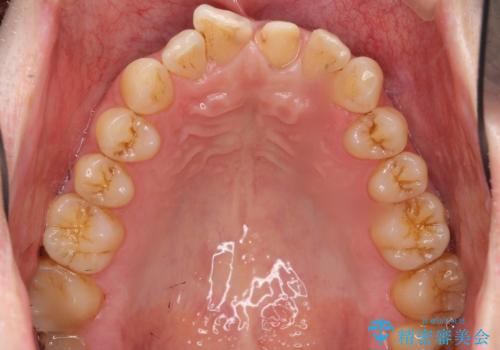

患者様のご希望により、最終補綴前にホワイトニングを行いました。

天然歯と見紛うほどの自然な仕上がりに喜んで頂けました。

クラウンの繊細なグラデーションや自然な表面性状・形態は熟練した技工士さんの技術の賜物です。

被せ物の種類:ジルコニアオールセラミッククラウン スペシャル